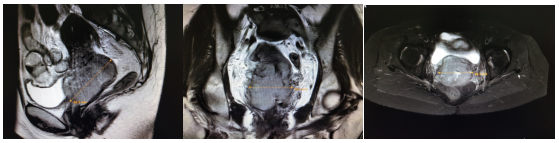

患者刘某某,女,50岁。患者4个月前无明显诱因出现阴道不规则流血,初始流血量较大,约为月经2倍,就诊于当地医院,给予对症处理后好转,故未进一步诊治。1个月前再次出现阴道流血,量多,色鲜红,就诊于当地某三甲医院,行阴道镜检查,提示宫颈局部病变恶性可能性大,遂进行病理活检,提示宫颈浸润性鳞状细胞癌,中分化。明确诊断后为求进一步治疗入我院。入院查体:外阴发育正常,已婚已产型,阴道通畅,粘膜润软,轻度充血,宫颈表面可见大小约5*4*4cm菜花样肿物,质糟脆,活动度差,触血(+),阴道前壁下1/3受累;子宫前位,大小及形态正常,活动度欠佳,无压痛;双附件区未触及明显异常,分泌物血性,量少。三合诊:双侧宫旁韧带结节样增厚,缩短明显,弹性差,达盆壁,肛门无异常,直肠粘膜光滑,指套未染血。入院盆腔核磁(图1):宫颈肿块伴宫颈积液,累及右侧输尿管并致右侧输尿管扩张积水;两侧髂血管走行区、左侧闭孔区、骶前脂肪间隙内淋巴结肿大,大部分考虑转移。结合查体及辅助检查,该患者明确诊断为宫颈恶性肿瘤(ⅢB期)。

放疗前盆腔核磁